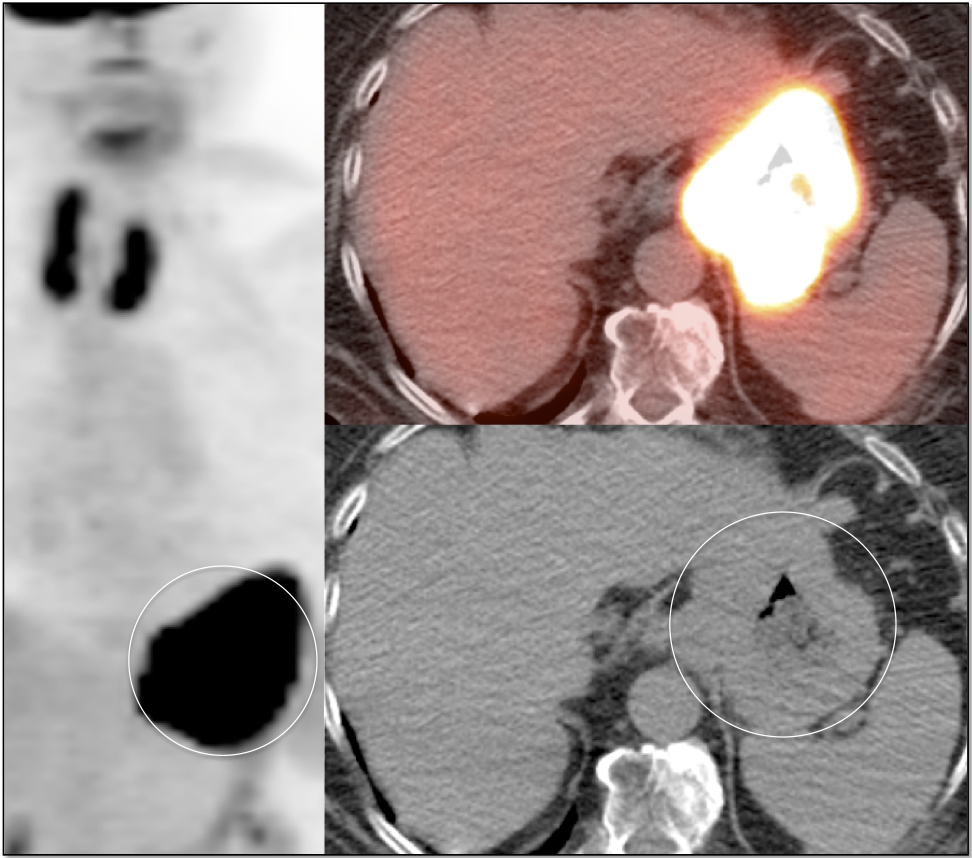

- Fusion of Images

- The Heterogeneous Liver

- Liver Ablation

- Little value in the assessment of tumor size or degree of wall invasion.

- The utility of PET/CT lies in its assessment of regional nodes and distant metastatic disease.

- Distant Disease: Most commonly to the liver, peritoneum, lung and bone.

Criteria for “Active Malignancy”:

The difficulty with PET/CT imaging and gastric cancer is that it is both easy to overlook and easy to over-call.

Normal FDG uptake involving the stomach can be extremely variable. It is not uncommon to see diffuse intense uptake throughout the entire stomach or intense uptake limited to only a segment of the stomach (fundus, body or antrum).